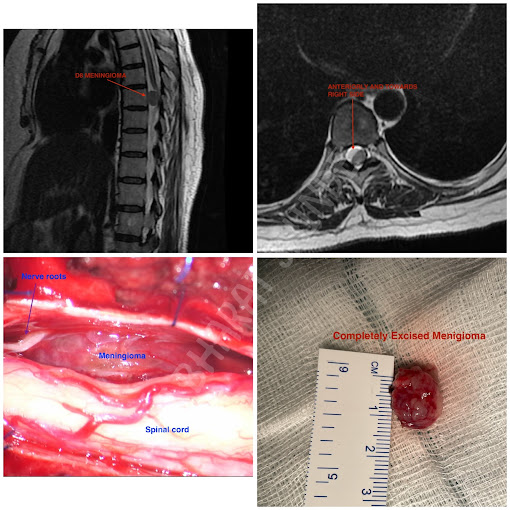

Dr Bharat Shinde completed his M.Ch Neurosurgery from the National Institute Of Mental Health And Neurosciences (NIMHANS), Bangalore which is an institute of National importance.